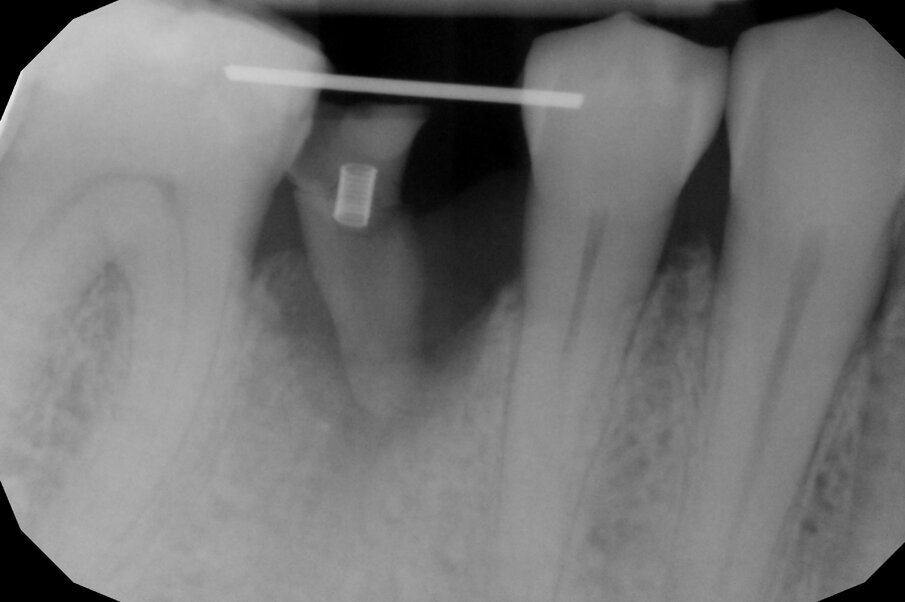

L’estrusione completa del frammento ha richiesto un tempo di 6 mesi, durante i quali è stata modificata più volte l’inclinazione della molla per evitare che il movimento diventasse ortogonale al segmento e mantenere la traiettoria prevista. Così facendo, è stato possibile rigenerare naturalmente l’intero alveolo e inserire, dopo 3 mesi di ulteriore maturazione del tessuto, in un contesto osseo ideale e perfettamente rigenerato un impianto Syra (Sweden & Martina) di diametro 4.25 mm e lungo 11 mm.

Dopo 3 mesi dall’inserimento implantare è stato possibile prendere un’impronta e di precisione e realizzare una corona singola avvitata.